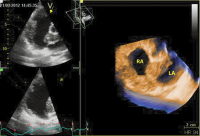

Echo

Abbildung 5: Dreidimensionaler Schnitt durch die Raumforderung, welche den gesamten Vorhof umgibt. RA: rechter Vorhof; LA: linker Vorhof